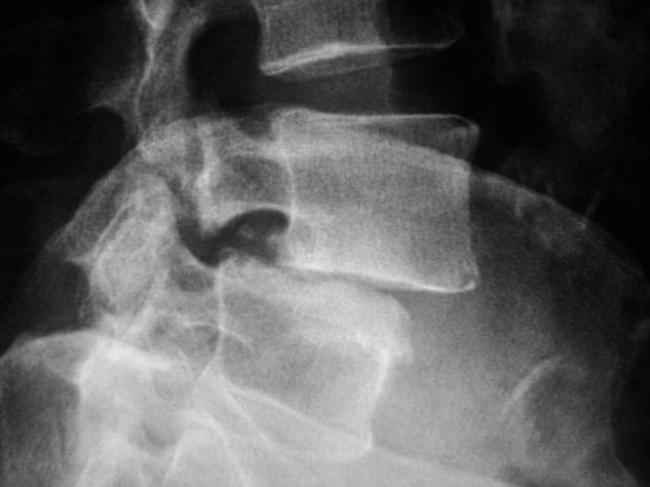

Подтвердить или опровергнуть диагноз позволяет рентген. Он определяет стадию развития заболевания и причину его возникновения. Более информативными методиками считается МРТ или КТ, но их назначают в отдельных случаях для получения развернутой картины состояния пациента.

Рентгеновский снимок является надежным способом обнаружить патологию